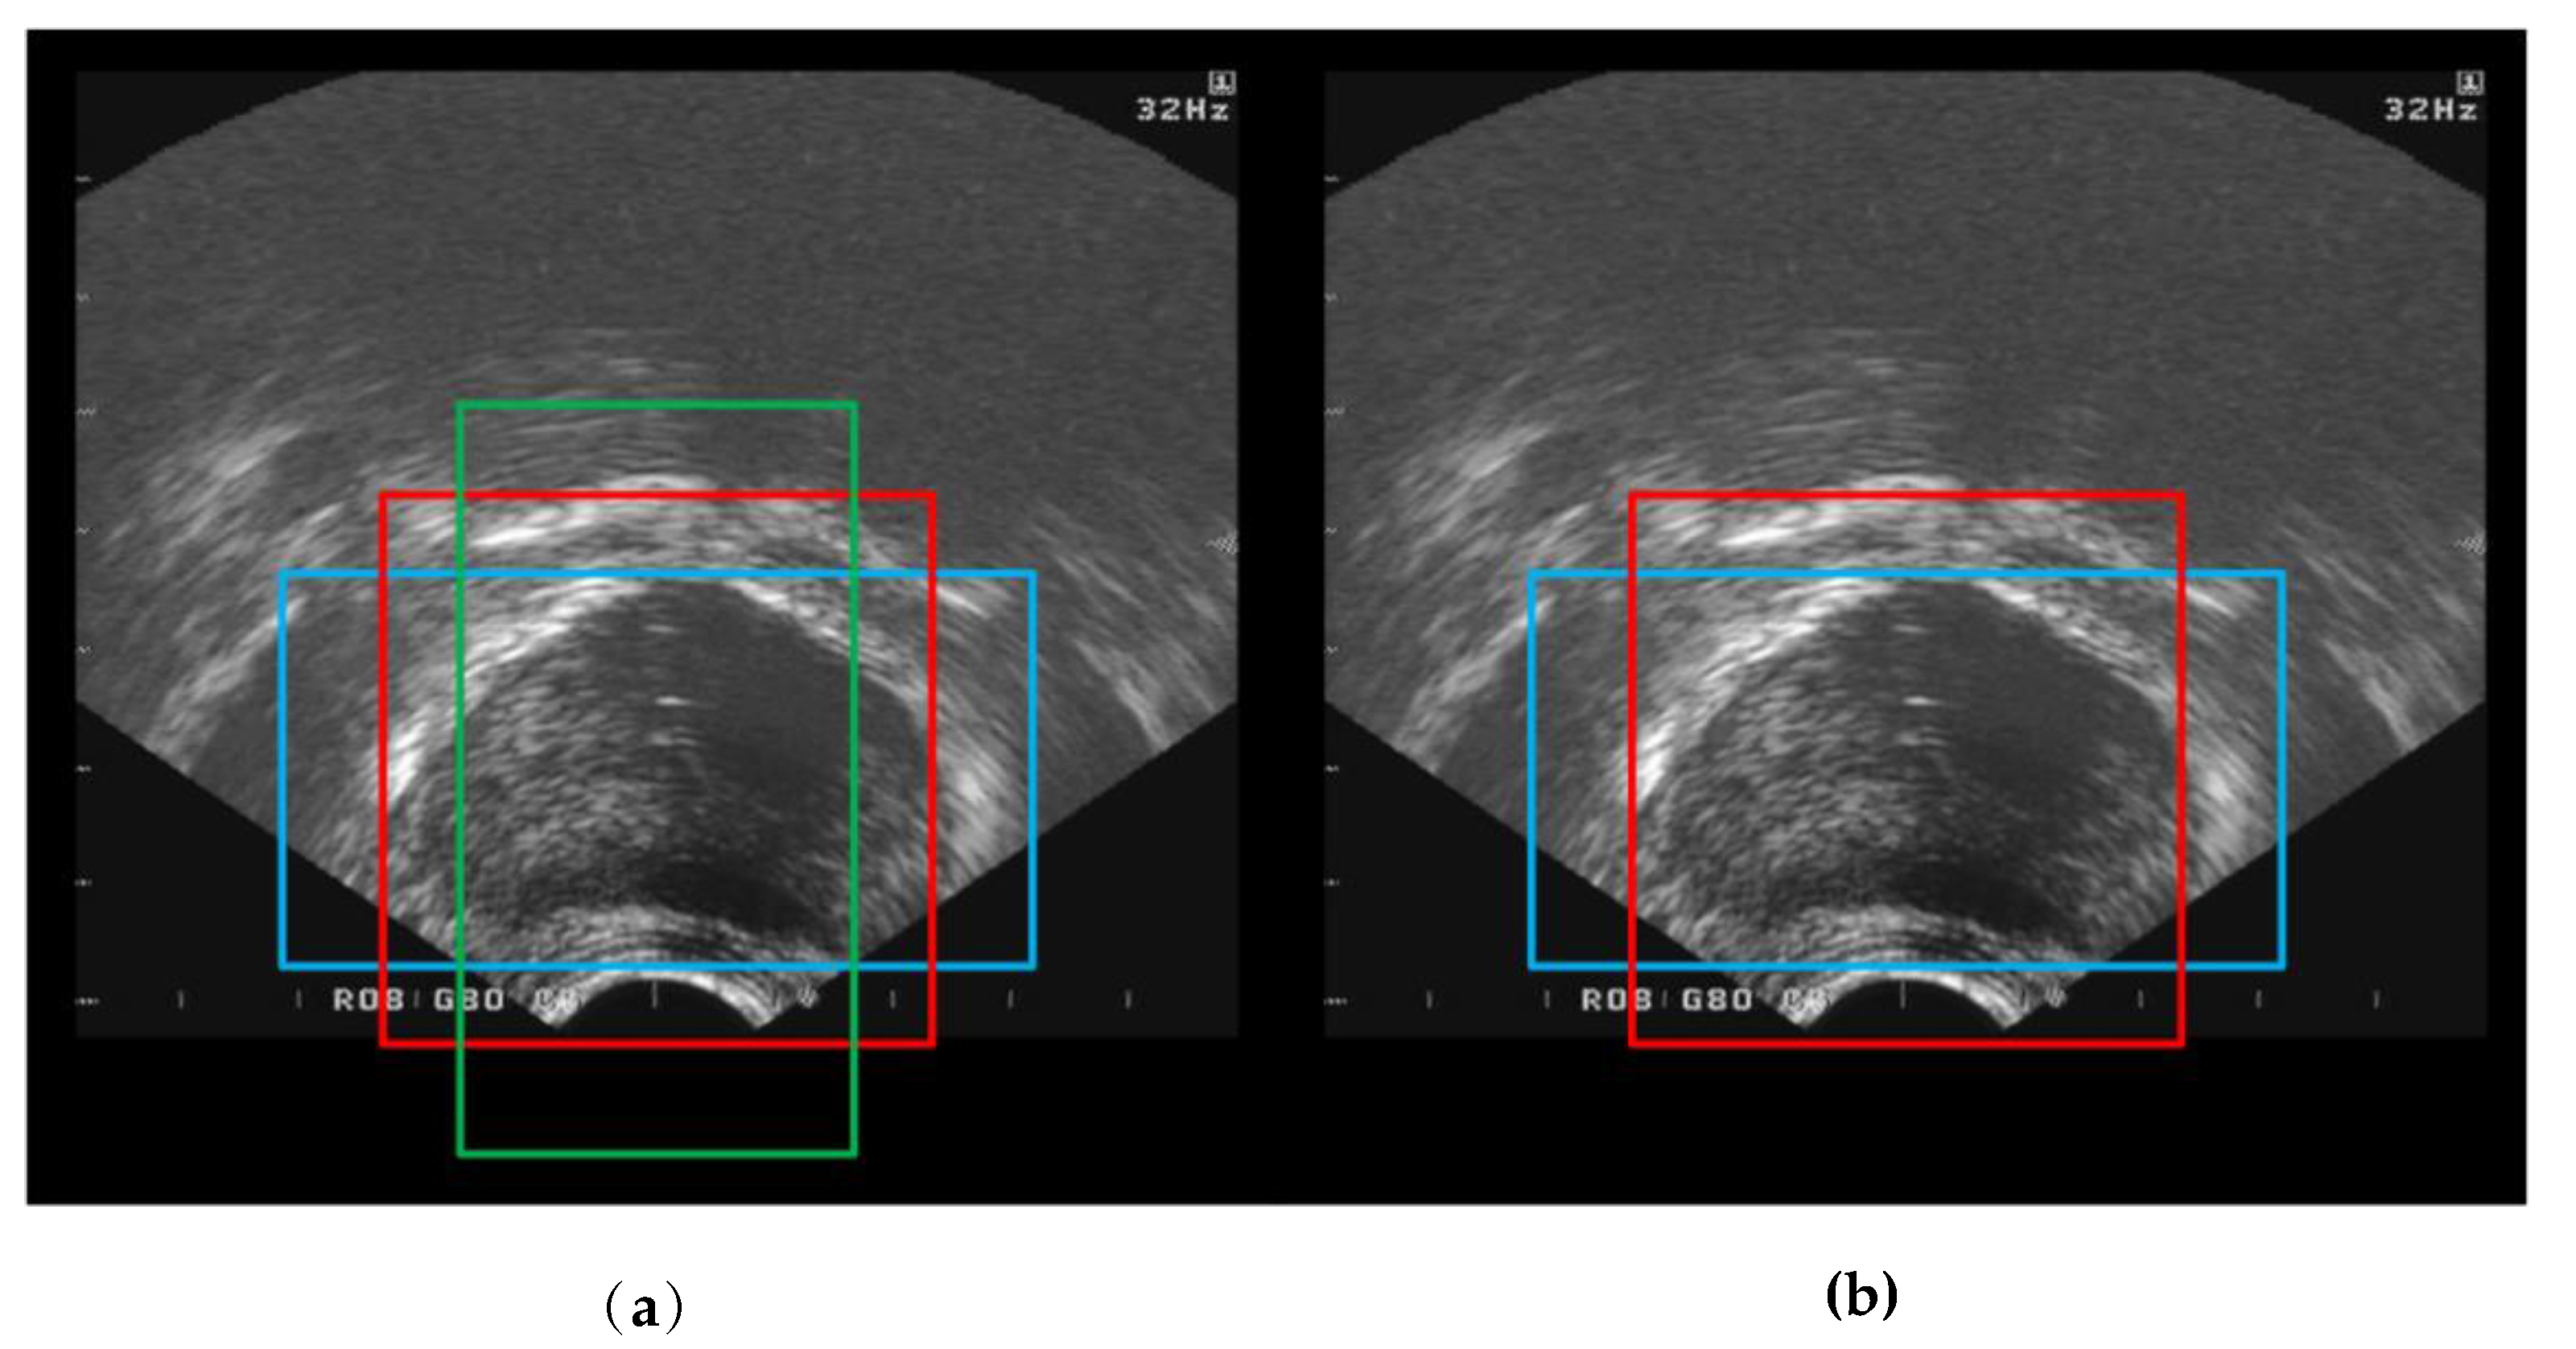

2.2. Target Area Screening Module

2.3. Target Area Screening Module